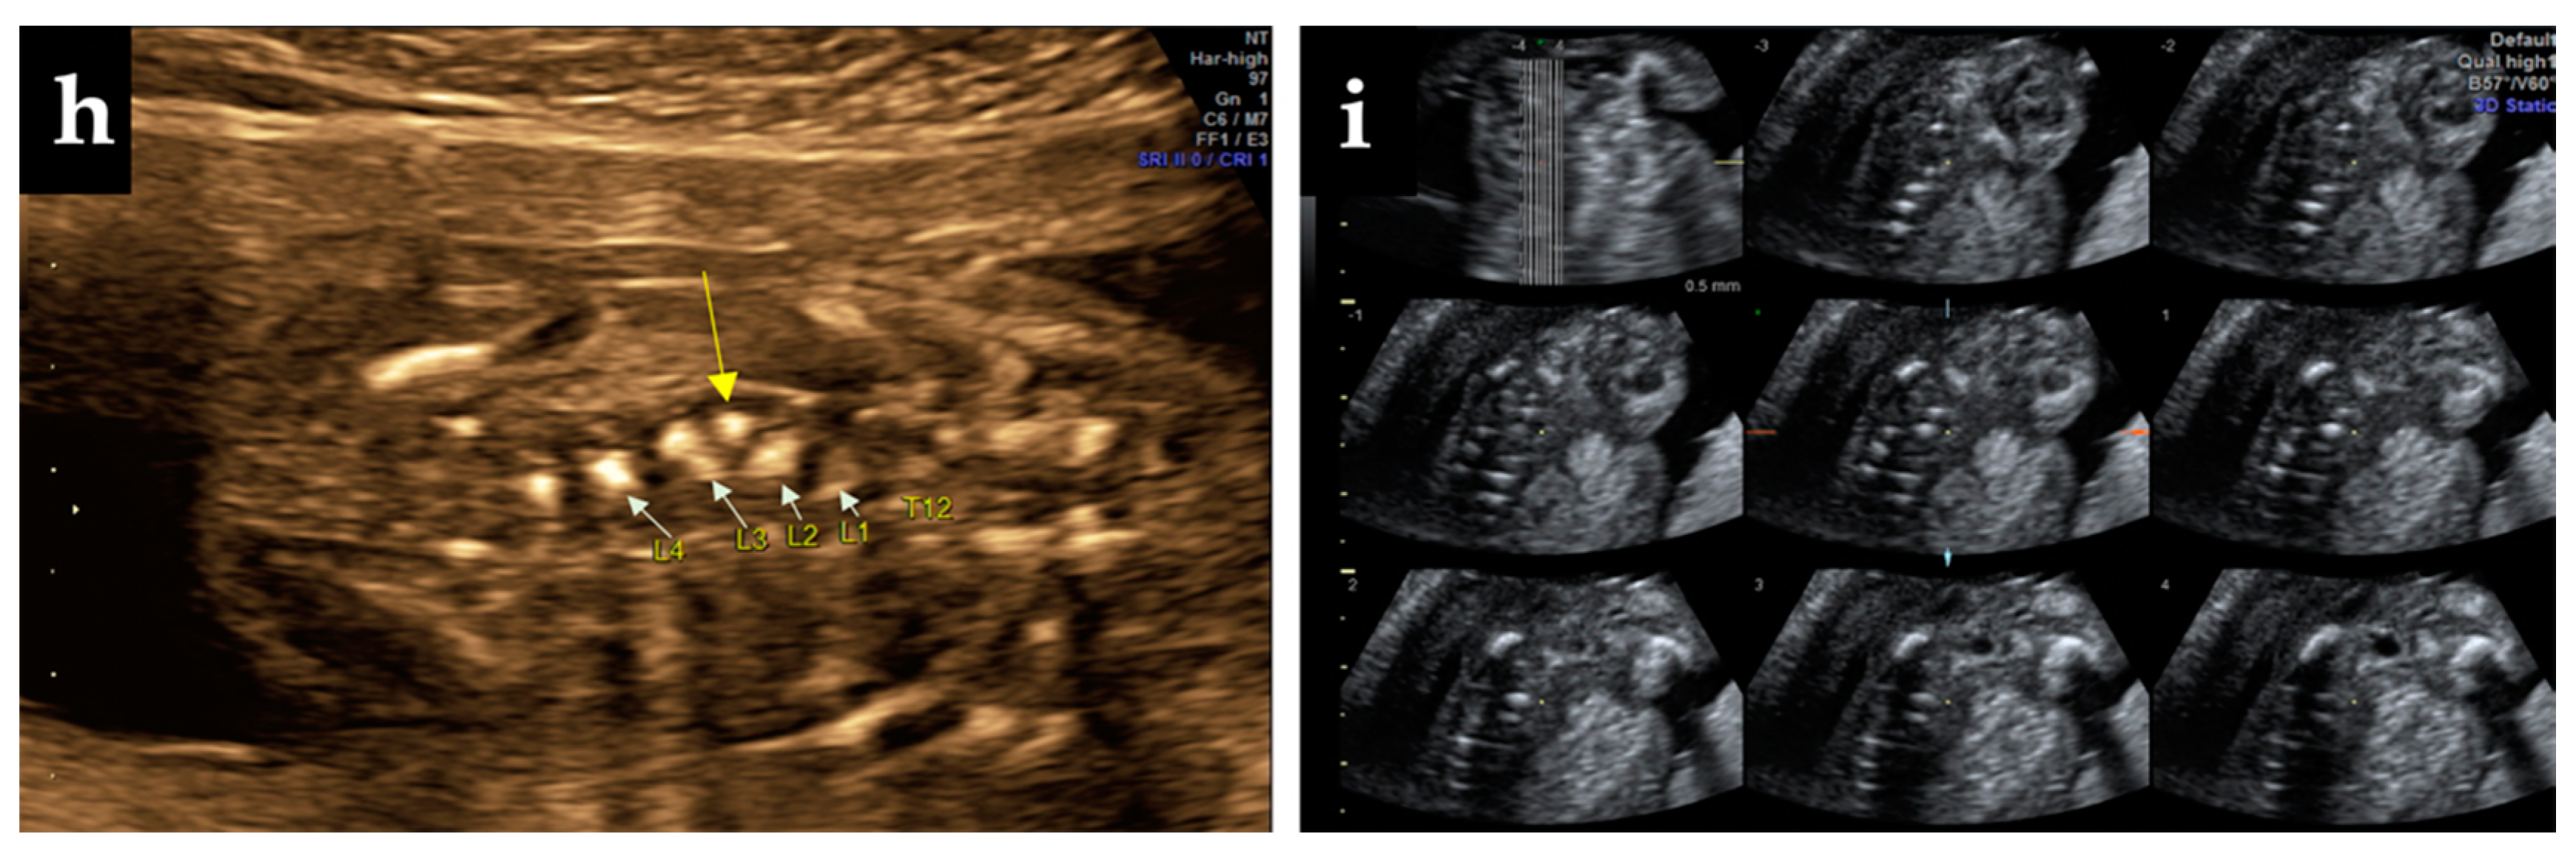

At 8 months after delivery, a routine consultation revealed the presence of an approximately 3 × 4 cm wide plaque on the right of the spine, without reflection at the skin, with mild scoliosis, suggesting the welding of the transverse process L3–L4 (Figure 2).

Figure 2.

At 8 months after delivery, a physical examination identified a mild scoliosis (red line) and rectangular zone (interrupted yellow line) in front of the transverse process L3–L4.

X-ray postnatal evaluation confirmed the early prenatal ultrasonographic diagnosis (Figure 3a). The parents refused further complementary imaging (MRI) despite the medical advice. The X-ray performed in the current year revealed in the anterior-posterior face X-ray of the thoracolumbar child’s spine, the hemivertebra, along with a mild scoliosis (Figure 3b,c).

Figure 3.

X-ray findings: (a) anteroposterior face of the child’s spine at 8 months after delivery indicating hemivertebra (yellow arrow); (b) anteroposterior X-ray face of the patient spine at 4-years-old depicting hemivertebra (yellow arrow) and scoliosis (red line), (c) lateral profile of the spine focused on the thoracolumbar section revealed the hemivertebra (yellow arrow), and curvature of the spine (red line).